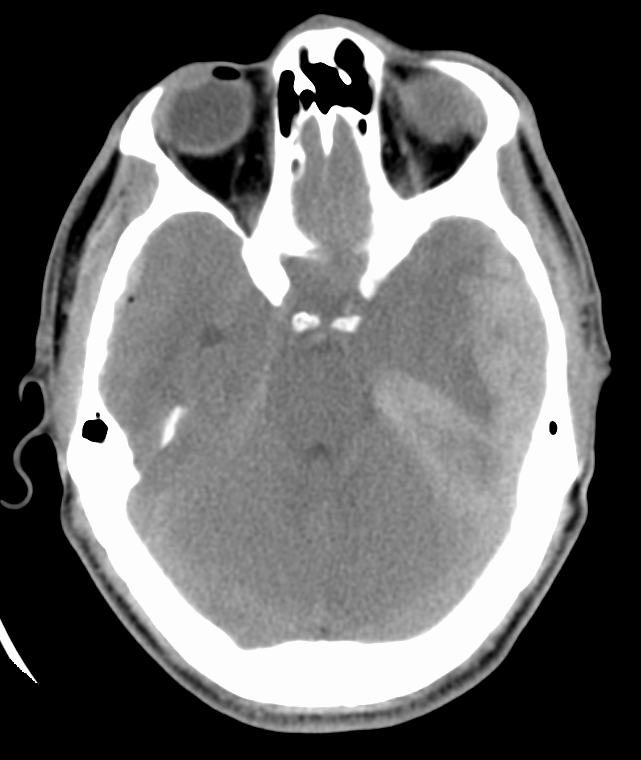

The patient is a female in her 60s who presents by EMS after a fall in a parking lot approximately one hour prior to arrival.  She fell forward and landed on her face.  She believes she simply tripped and fell, but she did lose consciousness and does not know how she ended up on the ground.  Per family, she is unsteady on her feet and falls frequently, requiring a cane at baseline.  She reports feeling “weak” but no other symptoms preceding her fall.  She presents with significant right-sided facial trauma and is unable to open her right eye. She has no complaints of blurry vision in her left eye.  She has no headache or other areas of pain or trauma.